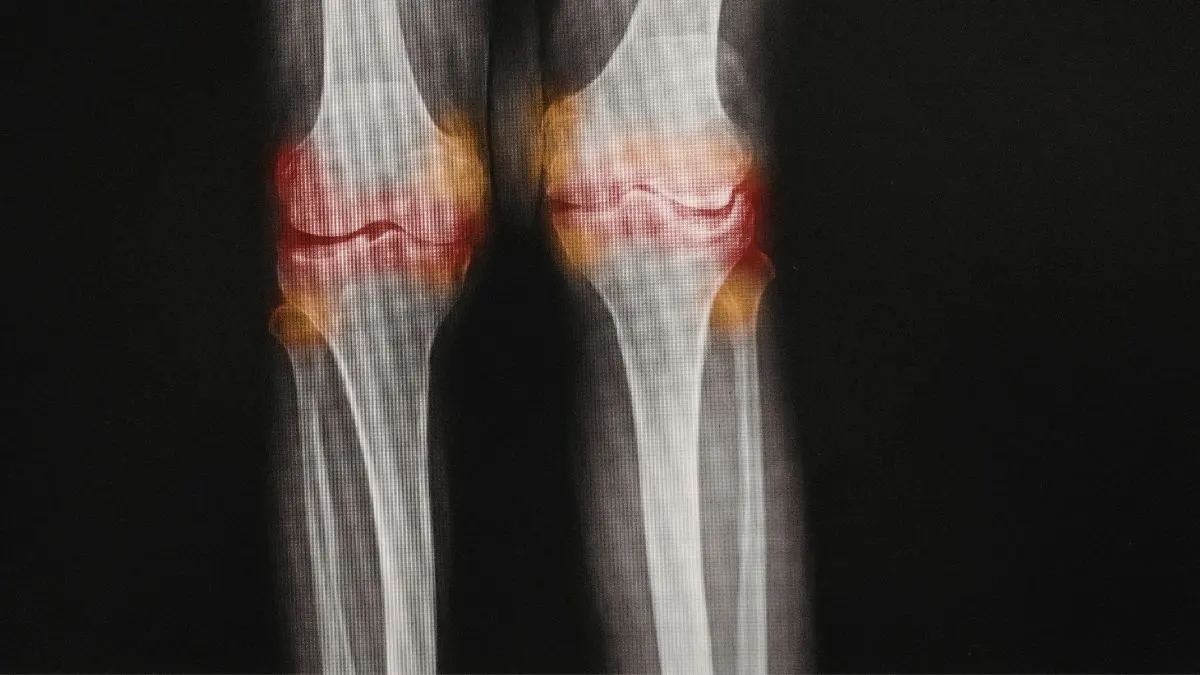

2. The Inflammaging Trap: Why Your Joints Ache?

Have you heard of inflammaging? It is a mix of the words inflammation and aging. Stress makes this process much worse. It acts like a match to a fire. Recent data shows that people over 60 with high stress have 40% higher CRP levels. CRP is a marker for inflammation that doctors find in your blood.

This leads to more joint pain and stiffness. It can even trigger arthritis. But it doesn’t stop at your joints. This low grade fire spreads to your organs. It makes it harder for your body to process sugar. This raises your risk for type 2 diabetes. Lowering your stress is about protecting your metabolic health. It stops systemic inflammation before it causes lasting damage.